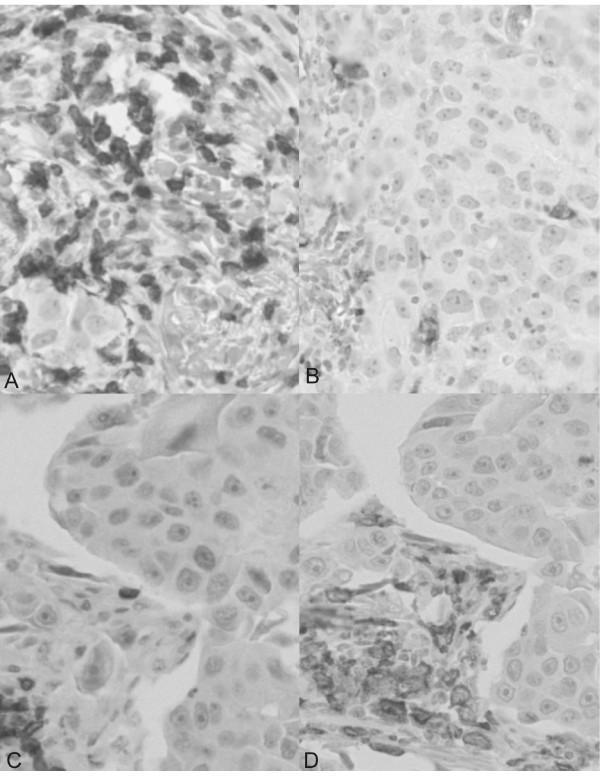

A tissue microarray (TMA) including 894 ductal and 164 lobular breast cancers was stained with antibodies recognizing CD4, FOXP3, and IL-17 by standard immunohistochemical techniques. Lymphocyte counts were correlated with clinico-pathological parameters and survival.

CD4(+) lymphocytes were more prevalent than FOXP3(+) TILs whereas IL-17(+) TILs were rare. Increased numbers of total CD4(+) and FOXP3(+) TIL were observed in ductal, as compared with lobular carcinomas. High grade (G3) and estrogen receptor (ER) negative ductal carcinomas displayed significantly (p < 0.001) higher CD4(+) and FOXP3(+) lymphocyte infiltration while her2/neu over-expression in ductal carcinomas was significantly (p < 0.001) associated with higher FOXP3(+) TIL counts. In contrast, lymphocyte infiltration was not linked to any clinico-pathological parameters in lobular cancers. In univariate but not in multivariate analysis CD4(+) infiltration was associated with significantly shorter survival in patients bearing ductal, but not lobular cancers. However, a FOXP3(+)/CD4(+) ratio > 1 was associated with improved overall survival even in multivariate analysis (p = 0.033).